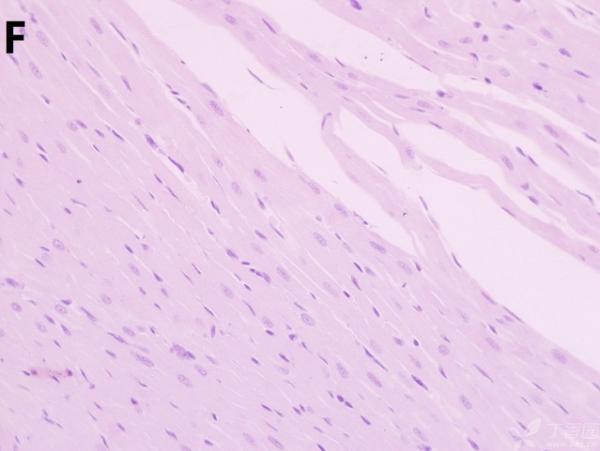

ÎÒ½«Ã¿¸ö×éÖ¯ÅÄÁË3¸öÊÓÒ°£¬ÒÔ±ã×ۺϷÖÎö£¬Âé·³¸÷λ°ïÎÒ°ÑA¡¢B¡¢C¡¢D¡¢E¡¢F¡¢GµÄËðÉË´óСÅŸö˳Ðò ÔÙ°ÑA¡¢B¡¢C¡¢H¡¢I¡¢JËðÉ˵ÄÑÏÖØ³Ì¶ÈÅŸöÐò¡£¸ÃÎÊÌâÒ²ÔÚ¶¡ÏãÔ°ÉÏÇóÖúÁË£¬Á´½Óhttp://www.dxy.cn/bbs/topic/23986562 A1.jpg A2.jpg A3.jpg B1.jpg B2.jpg B3.jpg C1.jpg C2.jpg C3.jpg D1.jpg D2.jpg D3.jpg E.jpg F1.jpg F2.jpg F3.jpg G1.jpg G2.jpg G3.jpg H1.jpg H2.jpg I.jpg I2.jpg I3.jpg J.jpg J2.jpg J3.jpg [ Last edited by ÀëÈËÏæÑÅÀá on 2012-10-9 at 21:11 ] |